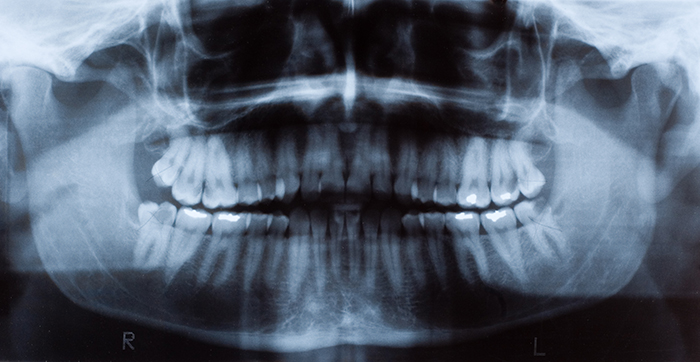

dental fillings

Tooth decay is the most prevalent chronic oral disease. The treatment for cavities, known medically as caries, is to remove the decayed tooth tissues and restore teeth with filling materials such as dental composites. Currently, composite restorations have a limited service life – about five to seven years -- and their replacement accounts for 60% of dental operations.

“The leading cause for the failure of composite restorations is the development of secondary caries caused by bacterial biofilms at the restoration margin,” notes Dr. Xu, who is also Director of Biomaterials Research at LSU Health New Orleans School of Dentistry.”Another cause is bulk fractures due to the weakness of the material.”